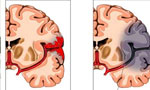

When a stroke occurs, every minute matters.

Each year, more than 795,000 people in the United States suffer a stroke, making it the third leading cause of death and the primary cause of adult disability.

Prompt treatment makes a big difference in outcome. The ability to provide care is based on the time a person first exhibits the symptoms of a stroke. The earlier a person is evaluated and treated by a stroke team, the greater the chance of lessening or reversing the effects of stroke. Knowing the signs and symptoms of a stroke can make the difference for you or a loved one.